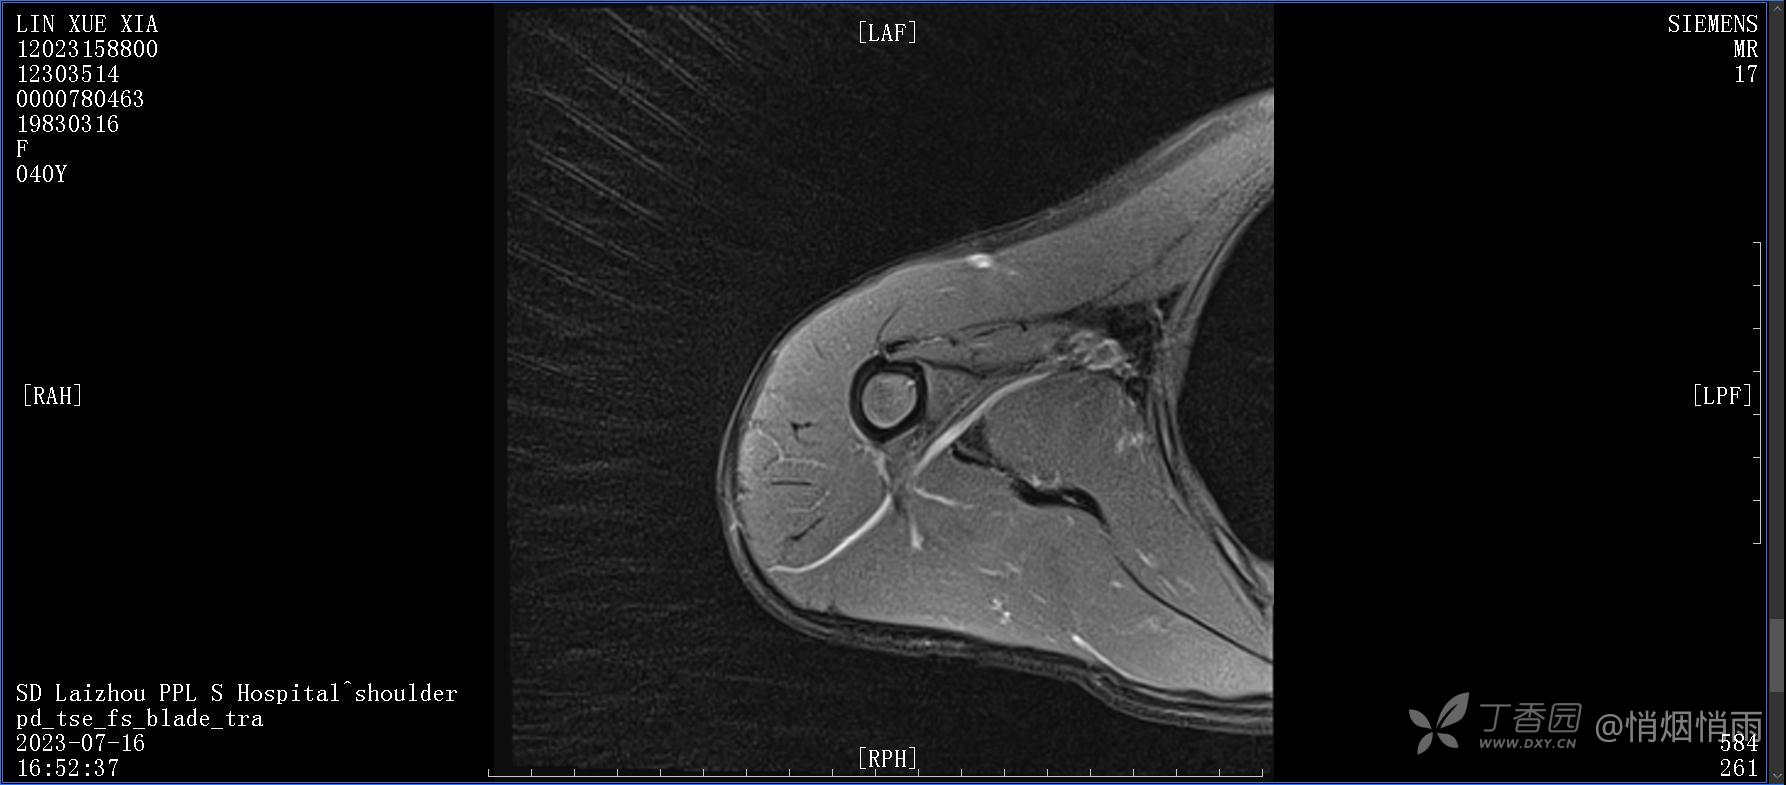

查体:右肩关节局部轻度肿胀,肩胛区压痛明显,痛处不固定,肩关节痛性活动受限,jobe test(+),lift -off test(+),中指、环指感觉较余指减退,余肢端感觉及血运情况可。

目前的诊断,暂时依据辅助检查诊为肩袖损伤,但是患者疼痛的性质和特点,却不是单纯的肩袖损伤所致。考虑过胸廓出口综合征,但是该疾病会出现肩胛区的疼痛吗?(由于考虑到费用的问题,没再进行下一步的检查)带状疱疹会有如此的症状吗?